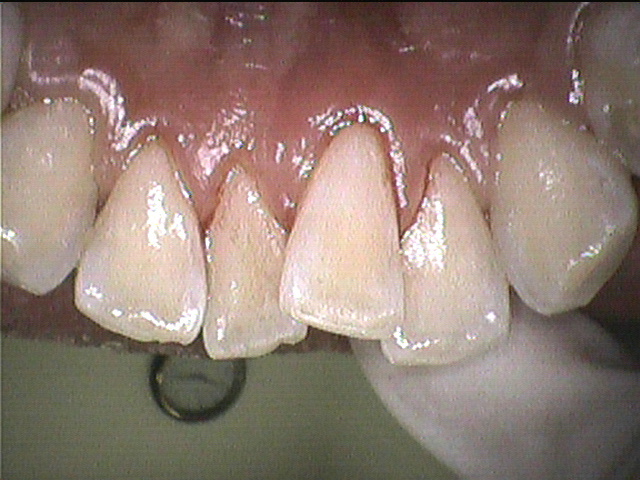

◎クリーニング後

綺麗になりました✨

フロスをほとんど使えていなかったそうで、歯間部にプラーク(歯垢)と歯茎に炎症がありました。

歯と歯が重なっているところは歯ブラシが当たりづらいため、歯石やプラーク(歯垢)がつきやすい場所です。